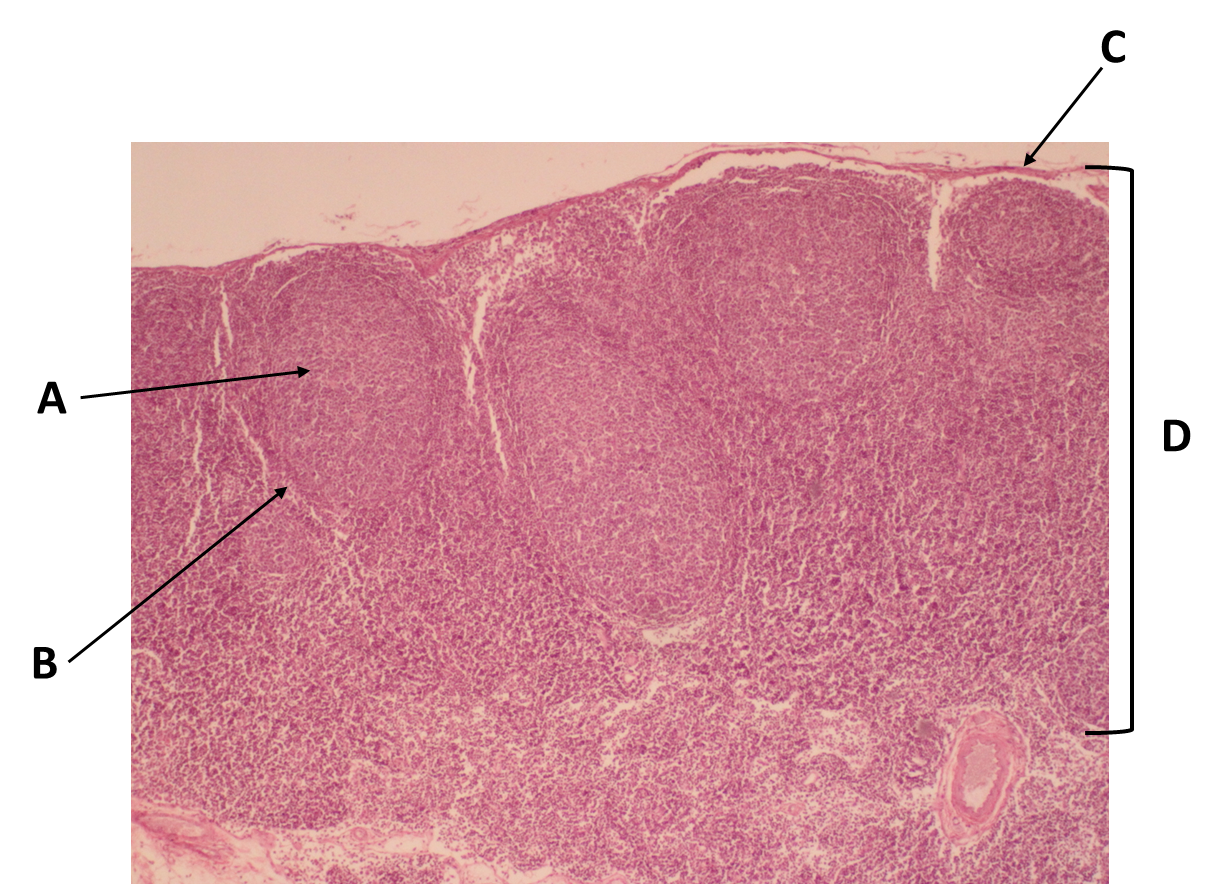

Identify the organ in this image.

thymus

Identify the structure labeled with the letter A

Germinal center

Identify the structure labeled with the letter B.

Follicle

Identify the area labeled with the letter A.

cortex